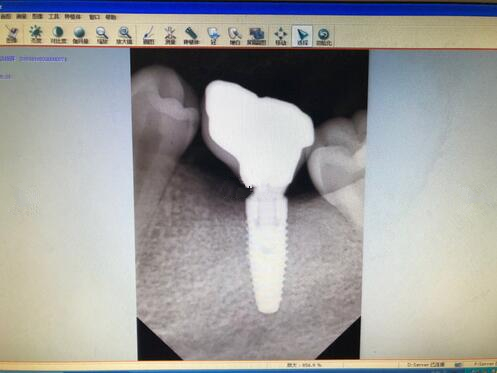

广州牙齿整形种植牙果图

在手术的过程中打了麻药,而且医生也一直在询问有没有什么不舒服的感觉,如果有不舒服,一定要第一时间告诉他,所以说还是比较舒适的整个过程。我的牙齿一共坏了四颗,所以说手术的时间还是比较久的,大概是用了将近三个小时的时间才完全结束,在这三个小时里面,口腔一直长着,还是觉得有一些口干的。

现在牙齿已经恢复的相当的好了,大家可以看到这几颗种植牙,看起来比之前的牙齿都更加好看了呢,而且更加的洁白也结实了不少,之前不敢吃的一些食物,现在都可以吃了。